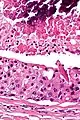

| Low magnification micrograph of a salivary duct carcinoma with characteristic comedonecrosis (left of image) adjacent to normal parotid gland (right of image). H&E stain. | |

Their histologic appearance is similar to ductal breast carcinoma.

Very low mag.

Intermed. mag.

Very high mag.